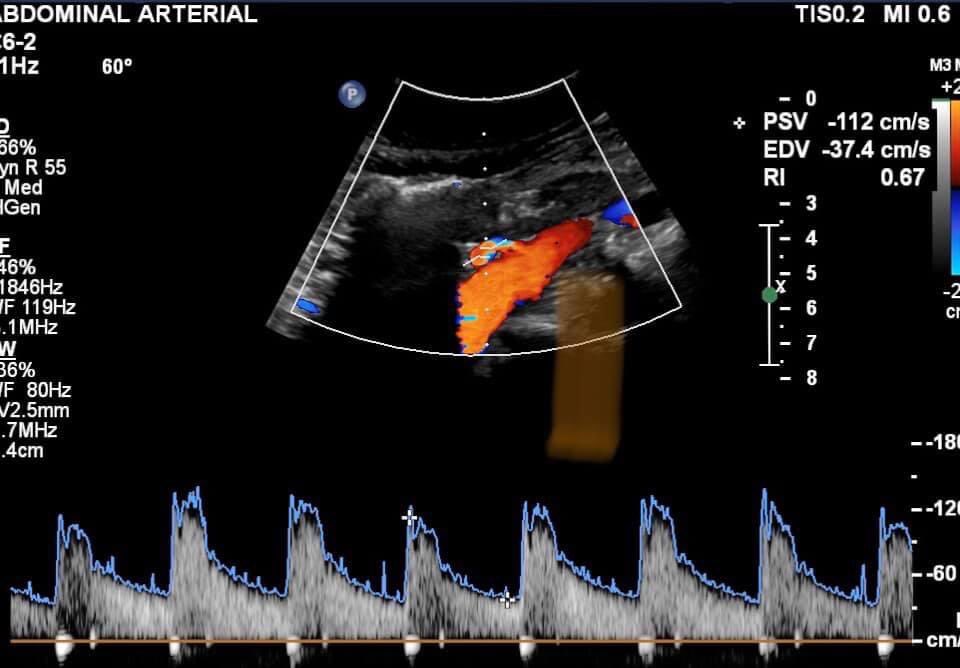

Incidental finding on aortoiliac examination. W, 62 years old, dyslipidemic and hypertensive. Artery emerging from the anterior wall of the infrarenal aorta, and in a caudal-cranial direction - RI: 0.67.

DUS: horseshoe kidney.

#dopplervascular